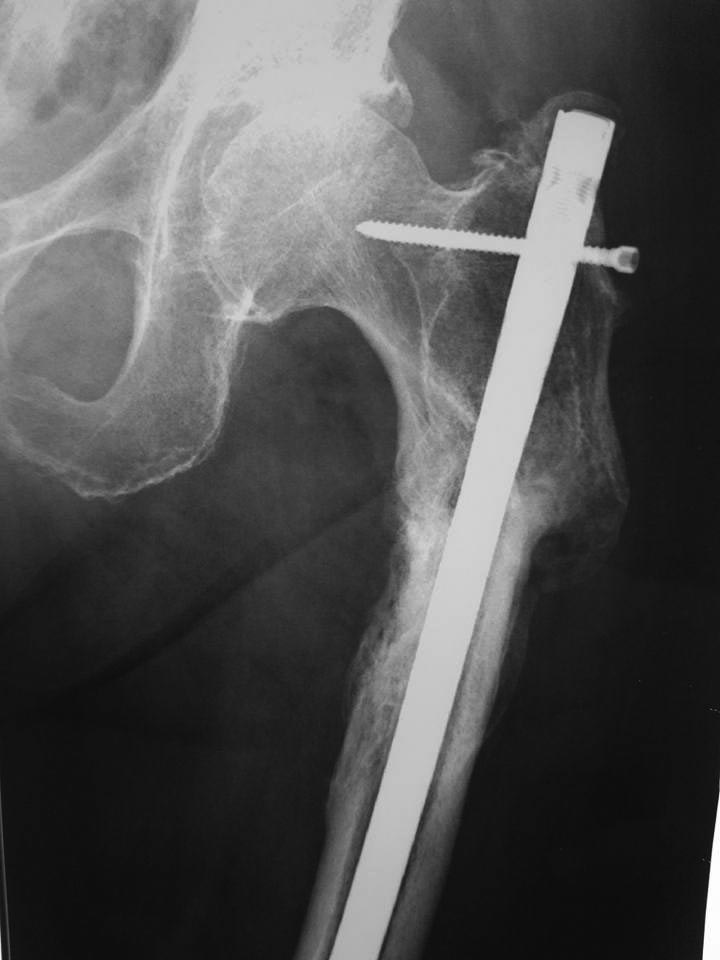

Посттравматическая варусная деформация бедра

Около года назад пациентка оперирована по поводу перелома бедра в Краснодарском крае. В марте 2016 г. удалены дистальные винты. В настоящее время беспокоят сильные и постоянные боли в области тазобедренного сустава.

Ограничено отведение в тазобедренном, сгибание в коленном. Пациентке 76, активная женщина. Какие варианты лечения? Имеет ли смысл удалять стержень?